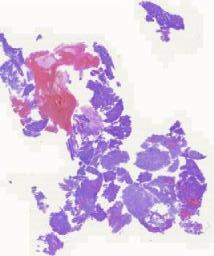

大体所见: 灰红灰白不整形组织多块,总体积2.5cm×2.0cm×0.5cm。